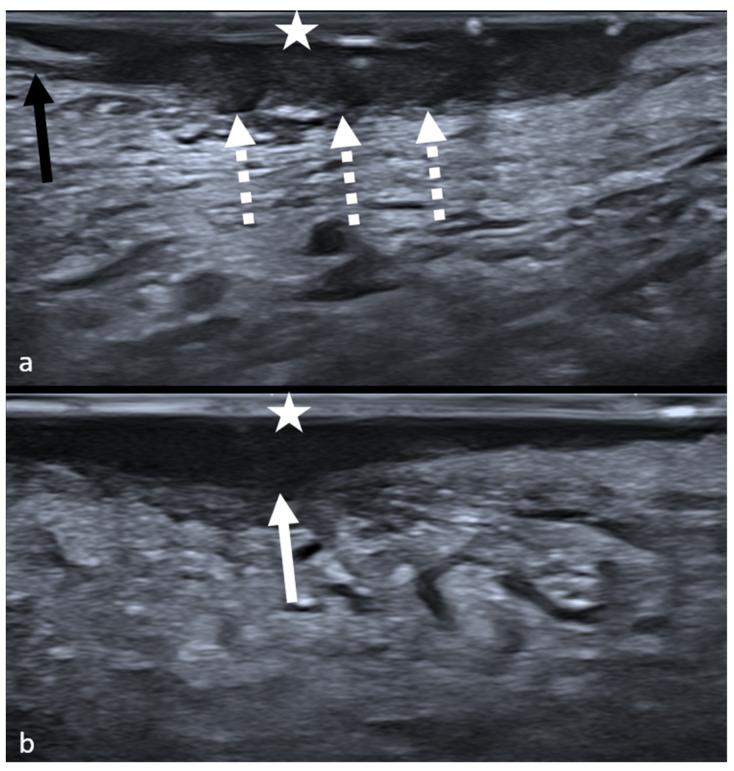

Despite advancements in multidisciplinary care, oncologic outcomes of oral cavity squamous cell carcinoma (OSCC) have not substantially improved: still, one-third of patients affected by stage I and II can develop locoregional recurrences. Imaging plays a pivotal role in preoperative staging of OSCC, providing depth of invasion (DOI) measurements. However, locoregional recurrences have a strong association with adverse histopathological factors not included in the staging system, and any imaging features linked to them have been lacking. In this study, the possibility to predict histological risk factors in OSCC with high-frequency intraoral ultrasonography (IOUS) was evaluated. Thirty-four patients were enrolled. The agreement between ultrasonographic and pathological DOI was evaluated, and ultrasonographic margins' appearance was compared to the Brandwein-Gensler score and the worst pattern of invasion (WPOI). Excellent agreement between ultrasonographic and pathological DOI was found (mean difference: 0.2 mm). A significant relationship was found between ultrasonographic morphology of the front of infiltration and both Brandwein-Gensler score ≥ 3 ( < 0.0001) and WPOI ≥4 ( = 0.0001). Sensitivity, specificity, positive predictive value, and negative predictive value for the IOUS to predict a Brandwein-Gensler score ≥3 were 93.33%, 89.47%, 87.50%, and 94.44%, respectively. The present study demonstrated the promising role of IOUS in aiding risk stratification for OSCC patients.